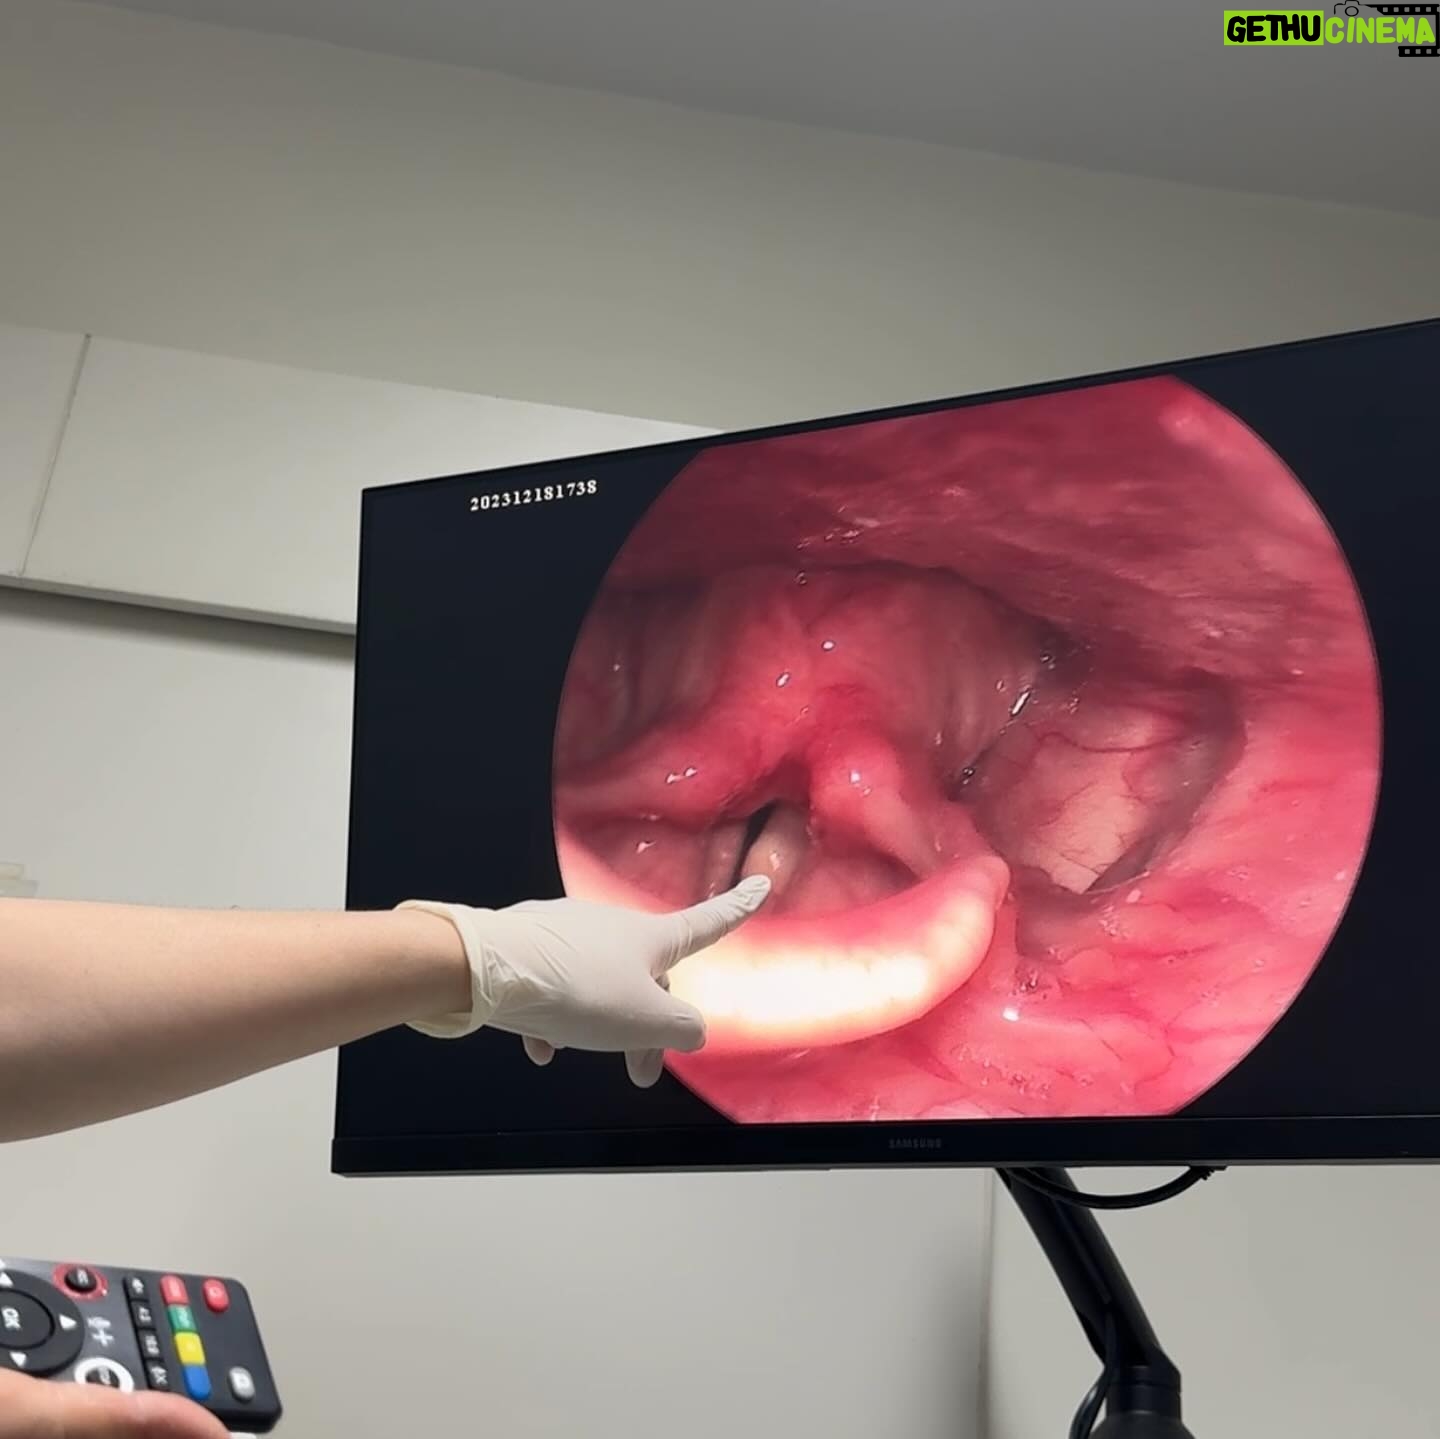

456.9K Likes – Danupha Khanatheerakul Instagram

Caption : สวัสดีค้าบ ส่งท้ายปีเก่าด้วยการ เป็นซีสต์ที่เส้นเสียง เย้ อ่าว ไม่ใช่ แฮะๆ หลังจากที่ใช้เสียงอยากต่อเนื่องไม่พักผ่อนนั้น มินก็เกิดอาหารคอแดงคอบวม (ซึ่งเป็นปกตินะฮะ เราพักผ่อนน้อยเองด้วย) เลยตัดสินใจไปตรวจที่โรงพยาบาลเฉพาะทาง และพบว่าตัวเป็น ซีสต์ที่เส้นเสียงข้างซ้ายข้างเดียว คือจะตัดออกก็ได้หรือจะปล่อยไว้ให้มันแตกเอง แต่มันก็อาจจะไม่แตกเองก็ได้ nobody knows คับ ถ้าผ่า โทนเสียงก็อาจจะเปลี่ยน แต่จริงๆคุณหมอบอกว่าไอ้ซีสต์นี้นวยก็น่าจะมีมาได้สักพักใหญ่ๆแล้วเนื่องจากโทนเสียงของนวยเปลี่ยนไปแล้วรอบนึง คือทุ้มต่ำลง ใช้เวลาตัดสินใจไป1สัปดาห์ ว่าจะผ่าตัดเอามันออก คือขึ้นชื่อว่าซีสต์ ตรงที่เส้นเสียงมันไม่ใช่ที่ที่มันควรอยู่อยู่แล้วอ่ะเนอะ ความจึ้งเกินอยู่ที่ว่า ก่อนหมอจะรมยาสลบ หนูสลบก่อนแล้ว กูหลับเบิ๊ดด หมอต้องปลุกมาดมยาสลบ55555 เลิศต่อมาคือ พอหมอสอดกล้องจะผ่าเอาอีก้อนออก ปรากฎว่า มัน already แตก แบบห๊ะ แบบร่างกายมัน heal ตัวเองไปแล้ว ซึ่งเป็นเรื่องดีนะคะ55555 เท่ากับว่าเราจะหายไวขึ้น ใช้เวลาพักฟื้นน้อยลง คุณหมอว่า โอกาสที่ซีสต์จะเองนี่ไม่ง่ายเลย แต่ก็ดีแล้วค่ะ หลังจากนั้นคือห้ามพูด สามวัน แต่ว่าอยากเล่าเรื่องราวให้พี่ๆฟังเลยส่งไปแบบคลิปสุดท้าย 5555555 สุดท้ายนี้ใครๆก็เป็นซีสต์ได้ รักษาเนื้อรักษาตัวไว้ด้วยนะคะทุกท่าน ปีนี้คงไม่ได้เจอกันในคอนแล้ว แต่อาจจะได้เจอมิลลิตามวัดหรือสถานที่สนุกๆนะคะ อิอิ เบิ้บบูทุกคนมากๆ ปีหน้าเจอกันใหม่ เสียงใสอย่างกับนกไนติงเกลค่ะ เสมอมาเสมอไป 🫶🏽✨Likes : 456898

456.9K Likes – Danupha Khanatheerakul Instagram

Caption : สวัสดีค้าบ ส่งท้ายปีเก่าด้วยการ เป็นซีสต์ที่เส้นเสียง เย้ อ่าว ไม่ใช่ แฮะๆ หลังจากที่ใช้เสียงอยากต่อเนื่องไม่พักผ่อนนั้น มินก็เกิดอาหารคอแดงคอบวม (ซึ่งเป็นปกตินะฮะ เราพักผ่อนน้อยเองด้วย) เลยตัดสินใจไปตรวจที่โรงพยาบาลเฉพาะทาง และพบว่าตัวเป็น ซีสต์ที่เส้นเสียงข้างซ้ายข้างเดียว คือจะตัดออกก็ได้หรือจะปล่อยไว้ให้มันแตกเอง แต่มันก็อาจจะไม่แตกเองก็ได้ nobody knows คับ ถ้าผ่า โทนเสียงก็อาจจะเปลี่ยน แต่จริงๆคุณหมอบอกว่าไอ้ซีสต์นี้นวยก็น่าจะมีมาได้สักพักใหญ่ๆแล้วเนื่องจากโทนเสียงของนวยเปลี่ยนไปแล้วรอบนึง คือทุ้มต่ำลง ใช้เวลาตัดสินใจไป1สัปดาห์ ว่าจะผ่าตัดเอามันออก คือขึ้นชื่อว่าซีสต์ ตรงที่เส้นเสียงมันไม่ใช่ที่ที่มันควรอยู่อยู่แล้วอ่ะเนอะ ความจึ้งเกินอยู่ที่ว่า ก่อนหมอจะรมยาสลบ หนูสลบก่อนแล้ว กูหลับเบิ๊ดด หมอต้องปลุกมาดมยาสลบ55555 เลิศต่อมาคือ พอหมอสอดกล้องจะผ่าเอาอีก้อนออก ปรากฎว่า มัน already แตก แบบห๊ะ แบบร่างกายมัน heal ตัวเองไปแล้ว ซึ่งเป็นเรื่องดีนะคะ55555 เท่ากับว่าเราจะหายไวขึ้น ใช้เวลาพักฟื้นน้อยลง คุณหมอว่า โอกาสที่ซีสต์จะเองนี่ไม่ง่ายเลย แต่ก็ดีแล้วค่ะ หลังจากนั้นคือห้ามพูด สามวัน แต่ว่าอยากเล่าเรื่องราวให้พี่ๆฟังเลยส่งไปแบบคลิปสุดท้าย 5555555 สุดท้ายนี้ใครๆก็เป็นซีสต์ได้ รักษาเนื้อรักษาตัวไว้ด้วยนะคะทุกท่าน ปีนี้คงไม่ได้เจอกันในคอนแล้ว แต่อาจจะได้เจอมิลลิตามวัดหรือสถานที่สนุกๆนะคะ อิอิ เบิ้บบูทุกคนมากๆ ปีหน้าเจอกันใหม่ เสียงใสอย่างกับนกไนติงเกลค่ะ เสมอมาเสมอไป 🫶🏽✨Likes : 456898

456.9K Likes – Danupha Khanatheerakul Instagram

Caption : สวัสดีค้าบ ส่งท้ายปีเก่าด้วยการ เป็นซีสต์ที่เส้นเสียง เย้ อ่าว ไม่ใช่ แฮะๆ หลังจากที่ใช้เสียงอยากต่อเนื่องไม่พักผ่อนนั้น มินก็เกิดอาหารคอแดงคอบวม (ซึ่งเป็นปกตินะฮะ เราพักผ่อนน้อยเองด้วย) เลยตัดสินใจไปตรวจที่โรงพยาบาลเฉพาะทาง และพบว่าตัวเป็น ซีสต์ที่เส้นเสียงข้างซ้ายข้างเดียว คือจะตัดออกก็ได้หรือจะปล่อยไว้ให้มันแตกเอง แต่มันก็อาจจะไม่แตกเองก็ได้ nobody knows คับ ถ้าผ่า โทนเสียงก็อาจจะเปลี่ยน แต่จริงๆคุณหมอบอกว่าไอ้ซีสต์นี้นวยก็น่าจะมีมาได้สักพักใหญ่ๆแล้วเนื่องจากโทนเสียงของนวยเปลี่ยนไปแล้วรอบนึง คือทุ้มต่ำลง ใช้เวลาตัดสินใจไป1สัปดาห์ ว่าจะผ่าตัดเอามันออก คือขึ้นชื่อว่าซีสต์ ตรงที่เส้นเสียงมันไม่ใช่ที่ที่มันควรอยู่อยู่แล้วอ่ะเนอะ ความจึ้งเกินอยู่ที่ว่า ก่อนหมอจะรมยาสลบ หนูสลบก่อนแล้ว กูหลับเบิ๊ดด หมอต้องปลุกมาดมยาสลบ55555 เลิศต่อมาคือ พอหมอสอดกล้องจะผ่าเอาอีก้อนออก ปรากฎว่า มัน already แตก แบบห๊ะ แบบร่างกายมัน heal ตัวเองไปแล้ว ซึ่งเป็นเรื่องดีนะคะ55555 เท่ากับว่าเราจะหายไวขึ้น ใช้เวลาพักฟื้นน้อยลง คุณหมอว่า โอกาสที่ซีสต์จะเองนี่ไม่ง่ายเลย แต่ก็ดีแล้วค่ะ หลังจากนั้นคือห้ามพูด สามวัน แต่ว่าอยากเล่าเรื่องราวให้พี่ๆฟังเลยส่งไปแบบคลิปสุดท้าย 5555555 สุดท้ายนี้ใครๆก็เป็นซีสต์ได้ รักษาเนื้อรักษาตัวไว้ด้วยนะคะทุกท่าน ปีนี้คงไม่ได้เจอกันในคอนแล้ว แต่อาจจะได้เจอมิลลิตามวัดหรือสถานที่สนุกๆนะคะ อิอิ เบิ้บบูทุกคนมากๆ ปีหน้าเจอกันใหม่ เสียงใสอย่างกับนกไนติงเกลค่ะ เสมอมาเสมอไป 🫶🏽✨Likes : 456898

456.9K Likes – Danupha Khanatheerakul Instagram

Caption : สวัสดีค้าบ ส่งท้ายปีเก่าด้วยการ เป็นซีสต์ที่เส้นเสียง เย้ อ่าว ไม่ใช่ แฮะๆ หลังจากที่ใช้เสียงอยากต่อเนื่องไม่พักผ่อนนั้น มินก็เกิดอาหารคอแดงคอบวม (ซึ่งเป็นปกตินะฮะ เราพักผ่อนน้อยเองด้วย) เลยตัดสินใจไปตรวจที่โรงพยาบาลเฉพาะทาง และพบว่าตัวเป็น ซีสต์ที่เส้นเสียงข้างซ้ายข้างเดียว คือจะตัดออกก็ได้หรือจะปล่อยไว้ให้มันแตกเอง แต่มันก็อาจจะไม่แตกเองก็ได้ nobody knows คับ ถ้าผ่า โทนเสียงก็อาจจะเปลี่ยน แต่จริงๆคุณหมอบอกว่าไอ้ซีสต์นี้นวยก็น่าจะมีมาได้สักพักใหญ่ๆแล้วเนื่องจากโทนเสียงของนวยเปลี่ยนไปแล้วรอบนึง คือทุ้มต่ำลง ใช้เวลาตัดสินใจไป1สัปดาห์ ว่าจะผ่าตัดเอามันออก คือขึ้นชื่อว่าซีสต์ ตรงที่เส้นเสียงมันไม่ใช่ที่ที่มันควรอยู่อยู่แล้วอ่ะเนอะ ความจึ้งเกินอยู่ที่ว่า ก่อนหมอจะรมยาสลบ หนูสลบก่อนแล้ว กูหลับเบิ๊ดด หมอต้องปลุกมาดมยาสลบ55555 เลิศต่อมาคือ พอหมอสอดกล้องจะผ่าเอาอีก้อนออก ปรากฎว่า มัน already แตก แบบห๊ะ แบบร่างกายมัน heal ตัวเองไปแล้ว ซึ่งเป็นเรื่องดีนะคะ55555 เท่ากับว่าเราจะหายไวขึ้น ใช้เวลาพักฟื้นน้อยลง คุณหมอว่า โอกาสที่ซีสต์จะเองนี่ไม่ง่ายเลย แต่ก็ดีแล้วค่ะ หลังจากนั้นคือห้ามพูด สามวัน แต่ว่าอยากเล่าเรื่องราวให้พี่ๆฟังเลยส่งไปแบบคลิปสุดท้าย 5555555 สุดท้ายนี้ใครๆก็เป็นซีสต์ได้ รักษาเนื้อรักษาตัวไว้ด้วยนะคะทุกท่าน ปีนี้คงไม่ได้เจอกันในคอนแล้ว แต่อาจจะได้เจอมิลลิตามวัดหรือสถานที่สนุกๆนะคะ อิอิ เบิ้บบูทุกคนมากๆ ปีหน้าเจอกันใหม่ เสียงใสอย่างกับนกไนติงเกลค่ะ เสมอมาเสมอไป 🫶🏽✨Likes : 456898